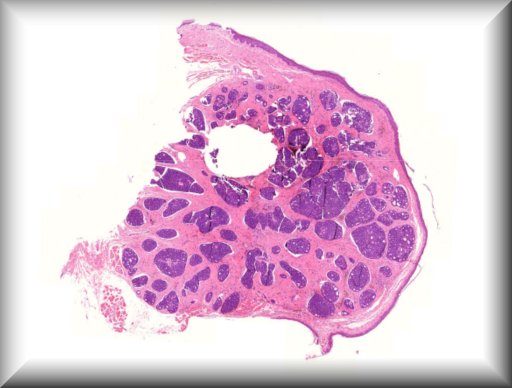

Hind M. Alkatan (Guest): A 10-month-old boy presented with a painless scrotal mass.External examination demonstrated left scrotal non-tender hard mass measuring 4x3 cm in size, with negative transillumination test. Ultrasonography of left scrotum showed a well-circumscribed, oval shaped mass with mixed echogenicity, The mass contained both cystic and solid component, with no clear visualization of the left testicle.The patient underwent left scrotal exploration with high inguinal orchidectomy |